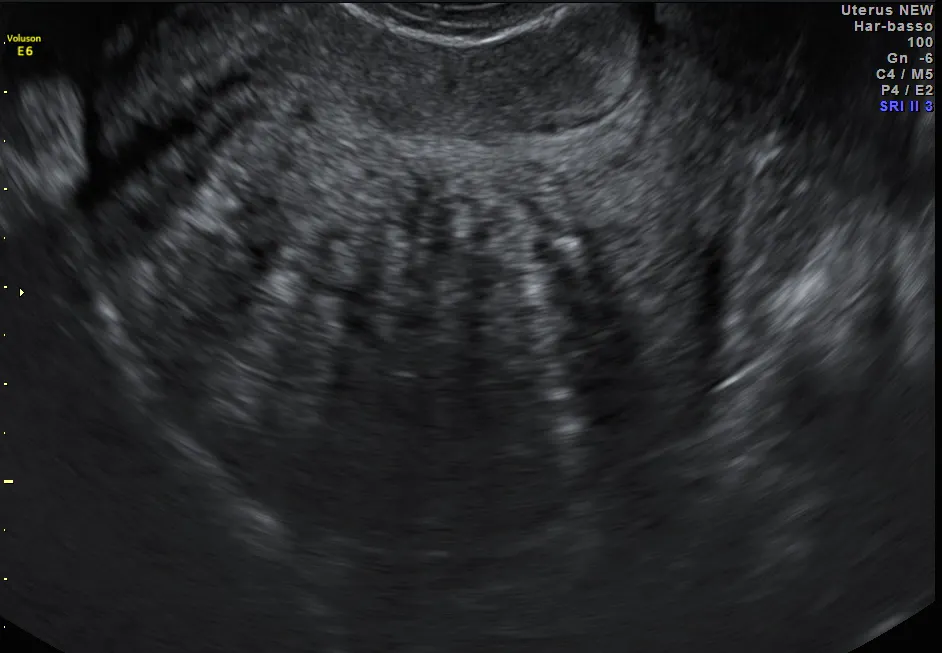

Heterogeneous myometrial echotexture A heterogeneous myometrial echotexture on ultrasound is usually a nonspecific finding, although it has been described with uterineUltrasound (US) is the accepted primary modality for the evaluation of abnormal uterine bleeding Sonohysterogram (SonoHSG) and magnetic resonance imaging (MRI) are useful for problem solving and when US is indeterminate A heterogeneous uterus is a term used to describe the appearance of the uterus after an ultrasound is conducted It simply means that the uterus is not totally uniform in appearance during the ultrasound According to MedHelp, there are two common causes of a heterogeneous uterus uterine fibroids and adenomyosis

–808 807 Sakhel and Abuhamad—Sonography of Adenomyosis Figure 5 Measurement of the length of a posterior uterine wall that is greater than that of the anterior wall (calipers) and has a heterogeneous myometrial echo texture Figure 4 Heterogeneous myometrium is more prevalent and consistent indicator for the diagnosis of adenomyosis by ultrasound Though enlarged uterus is almost invariably present in cases of adenomyosis (93%), yet it is totally nonspecific and is also present in multiparous females (see Figure 3, Figure 4) Download Download fullsize image;For postmenopausal women, transvaginal ultrasound evalua

Muscular hyperplasia and hypertrophy cause focal or diffuse myometrial thickening and globular uterine enlargement, often with thin "venetian blind" shadows The combination of these findings results in a heterogeneous myometrium, with blurring of the endometrial borderUnicornuate uterus is presented Abdominal and pelvic ultrasound revealed ahypertrophied right kidney measuring 130 cm, anormal right ovary, and absent left kidney and ovary Computerized tomography of the abdomen and pelvis confirmed absence of the left kidney and ovary and revealed aunicornuate uterus with absent left hornImaging of leiomyomas and their variants allows classification by location in the uterus and pretreatment planning Ultrasound is the firstline imaging modality because it is a costeffective portable realtime examination that provides good anatomic detail without radiation

Disruption of a subendometrial halo on ultrasound may be suggestive of myometrial involvement CT It means the texture of the uterus is not uniform on ultrasound A heterogeneous myometrial echotexture on ultrasound can be a non specific finding, of no significance, although it has been described with uterine adenomyosis, so talk to your doc about the results"plz explain my ultrsound report the anteverted uterus mesure 79x48x45mm a 6mm secretory phase endometrium is seen the left ovary measure 11cc and the right ovary measure 8cc no fluids or adnexal mass is seen the myometrium appears heterogeneous in ?" Answered by Dr Gerardo Guerra Bonilla Looking for?